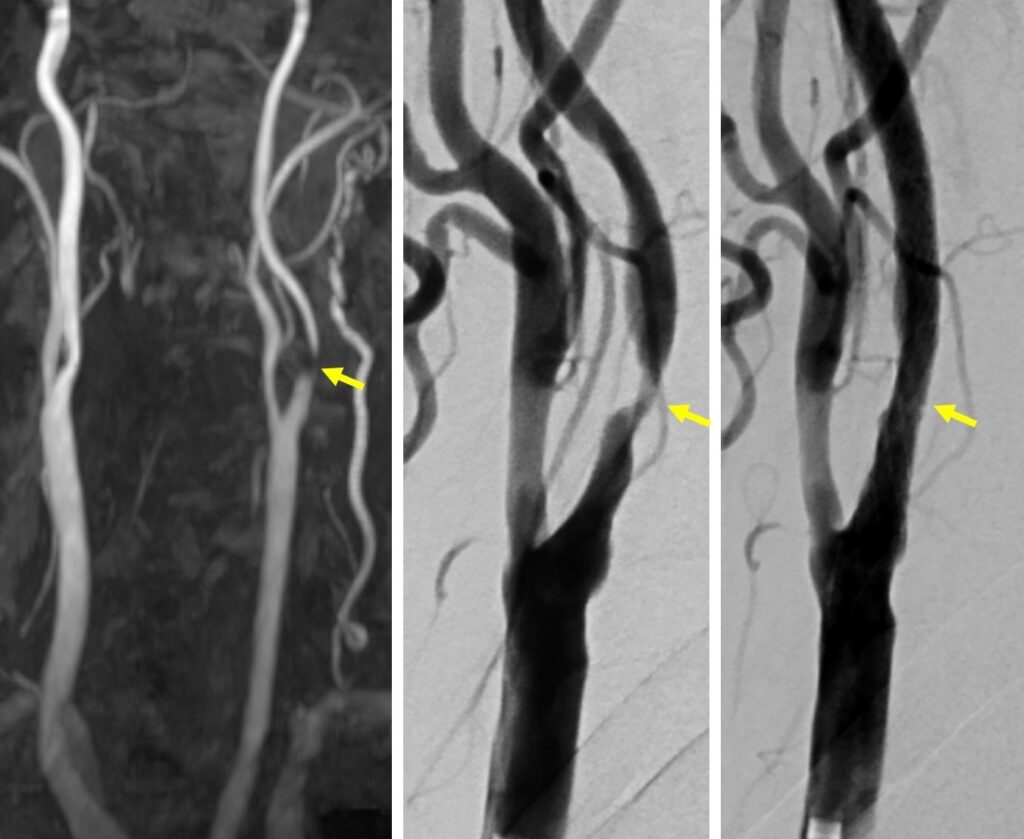

図の説明:左:MRAで頚部の頸動脈の高度狭窄を発見された(矢印)。中:カテーテル血管撮影で狭窄が確認された(矢印)。無症状であったが、高度狭窄であったためステント治療を行った。左; ステント留置により狭窄部の拡張が得られた(矢印)。